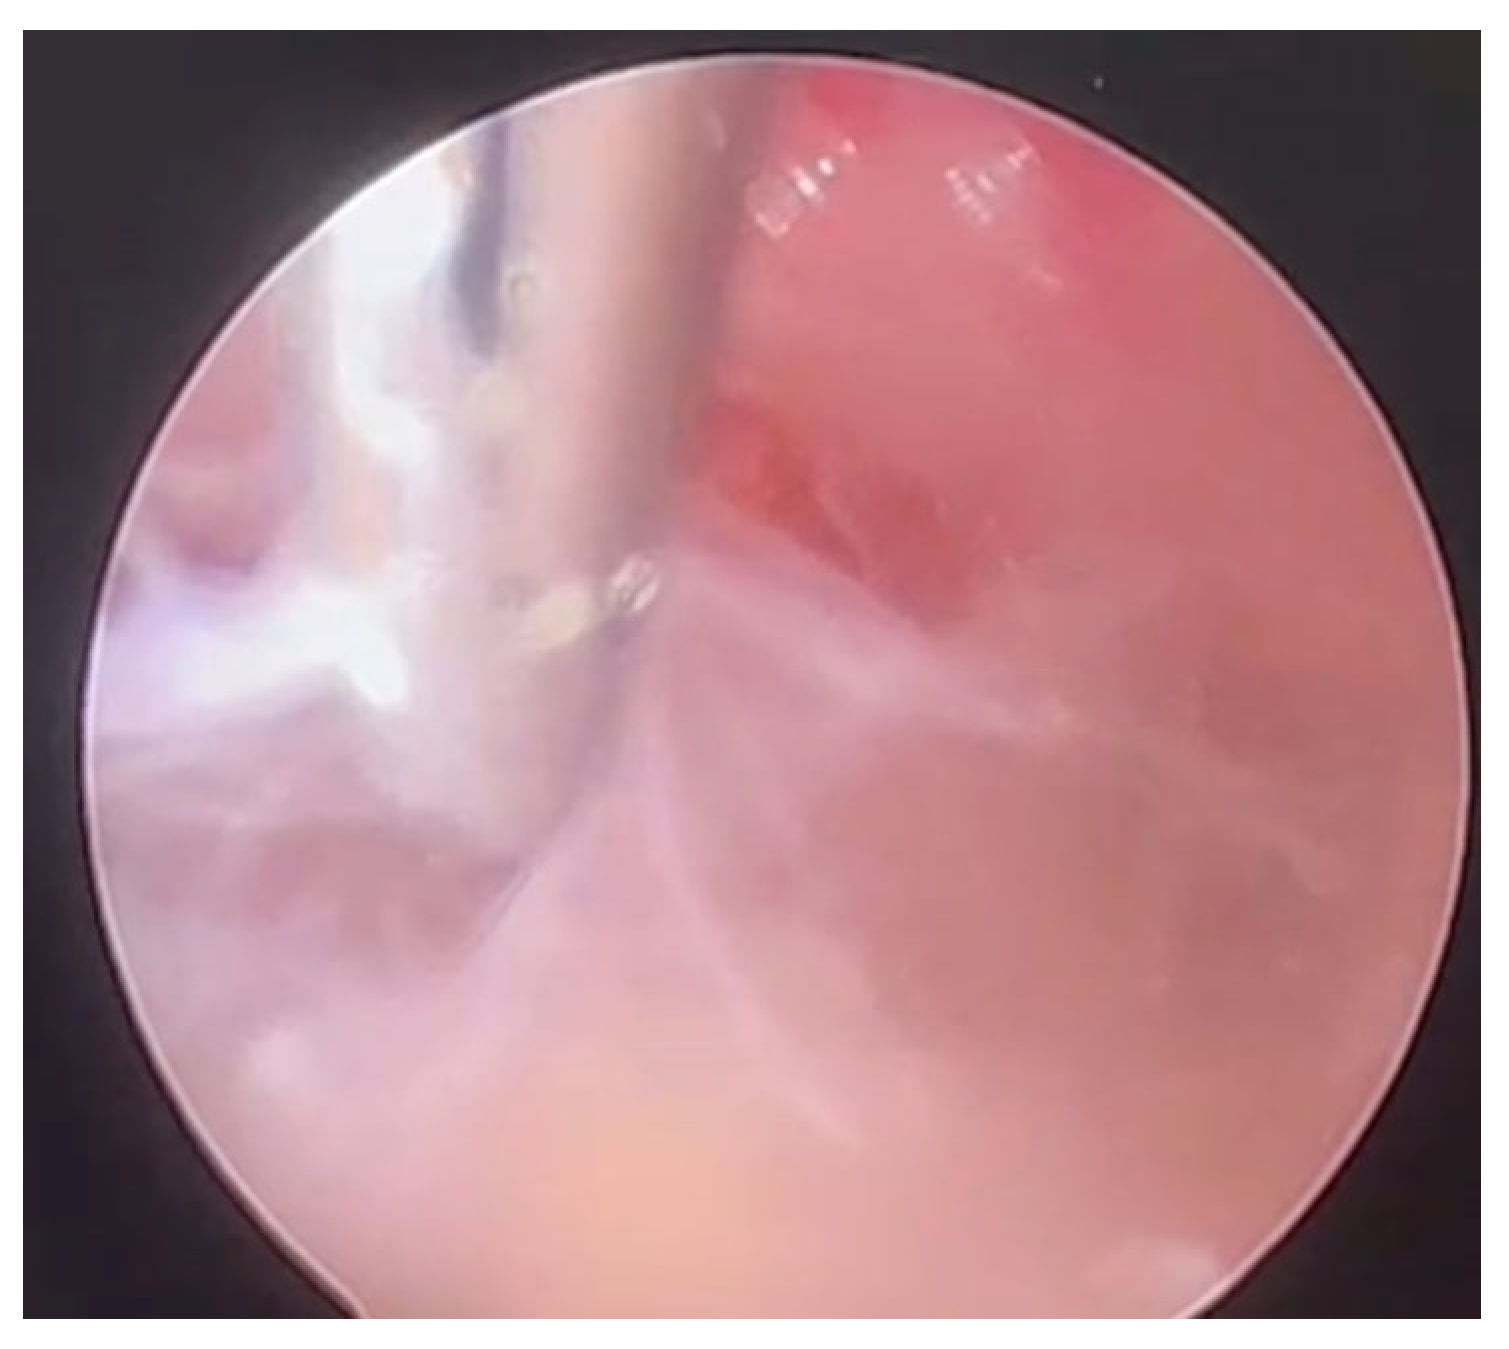

| 8 | Our case | 77/M | Fever, confusion | Right frontal lobe hyperintensity and left lateral ventricle exclusion. | Encephalitis and ventriculitis | CSF | Pleocytosis, hypoglycorrhachia, and hyperproteinorrachia | INH + RIF + EMB + LEV; LIN (2 weeks) | No | Yes | 14 | SR |